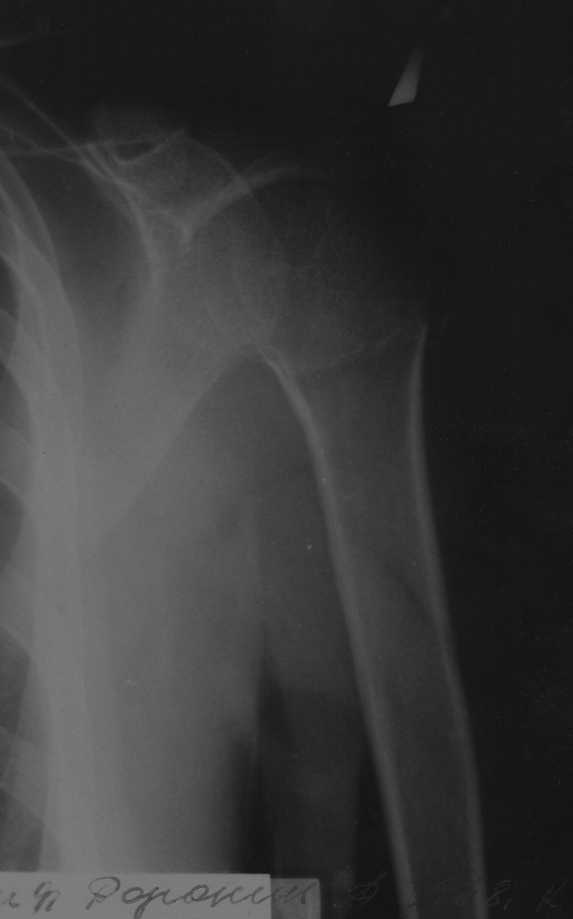

Закрытый оскольчатый перелом хир. шейки плеча со смещением |

Коллеги, мы тут рассходимся во мнениях. Больной, 30 лет, оскольчатый перелом шейки плеча со смещением, примерно две недели. В травмпункте закрытую репозицию делать не стали, от открытой также отказались, дескать, смещение незначительное, срастется и так, руку на косынку и отпустили.Пришел через две недели к нам. Состояние на снимке.Как лучше лечить дальше, как думаете? Консервативно, оперировать? Успех закрытой репозиции сомнитетелен, на мой взгляд.

Проблема -- смещение отломка, неудовлетворительный контакт, угроза нарушения функциональности (ограничение движений, если срастется так). Мнения разделились примерно пополам: лечить консервативно/прооперировать. Кроме того, пациент жалуется на сильные боли в суставе, которых, как мне кажется, на пятнадцатый день быть не должно.

Нельзя по одной проекции судить о положении отломков

Рентгенологические исследования проксимального отдела плеча состоит из прямого, бокового и аксиальных видов. Если имеются сложные переломы тогда рекомендуется Томография, а так в большинстве случаев достаточно бывает стандартных снимков.

Независимо от условий (нежелание рентгентехника или отсутствие пленок) необходимо добиться рентгенограмм, особенно аксиальной, потому что одна проекция не гарантирует, что не пропущен вывих в плечевом суставе.

Для принятия решения и исследования обычно достаточно пару дней, а здесь третья неделя, начало консолидации метафизарной части, надо спешить!